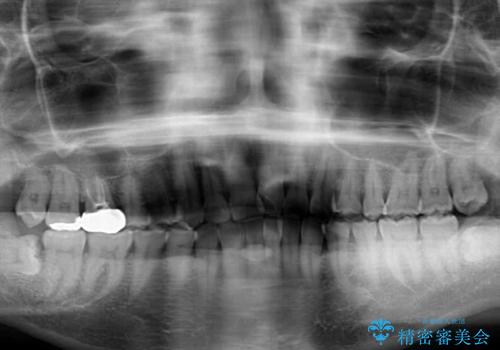

- 前歯のデコボコを治したいとのことで来院された患者様です。

上下顎ともに歯列全体の後方移動と側方拡大、IPR(歯と歯の間を削る)によってデコボコが解消するように設計し、インビザラインにより治療を行うこととしました。

後方移動に際し、上下の親知らずは4本とも抜歯することとしました。